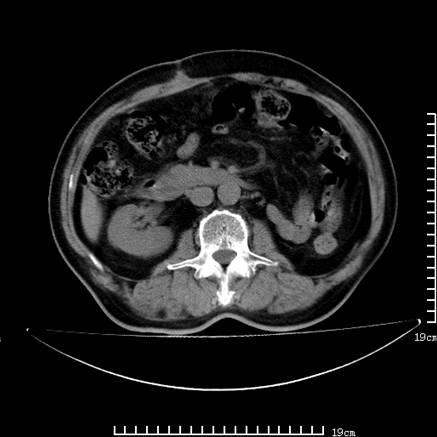

以下是引用zsl6918在2008-7-19 21:53:00的发言:[br]胆总管结石并胆系感染,胆囊切除术后改变。

以下是引用sch2008在2008-7-19 22:03:00的发言:[br]肝内胆管及胆总管积气,并胆总管结石,考虑;胆囊切除术后,胆系感染

以下是引用xinliheng001在2008-7-19 21:59:00的发言:[br]胰头段胆管结石肝内外胆管扩张积气。

以下是引用liaoqiang在2008-7-19 22:26:00的发言:[br]胆总管结石伴胆系感染。